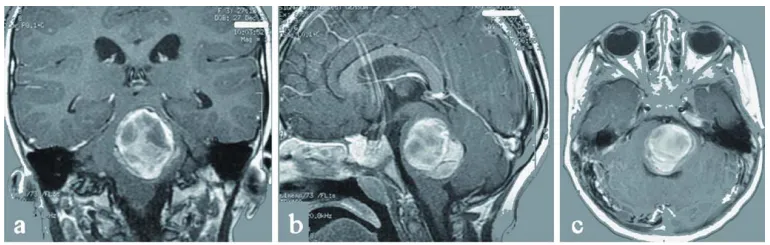

头痛、恶心、呕吐21岁的Lily从未想过,这些看似普通的症状,竟是脑干出血的征兆。 作为一名在校大学生,她原本对未来充满期待,直到在当地医院ICU醒来,得知自己脑干深处长了一个巨大的...